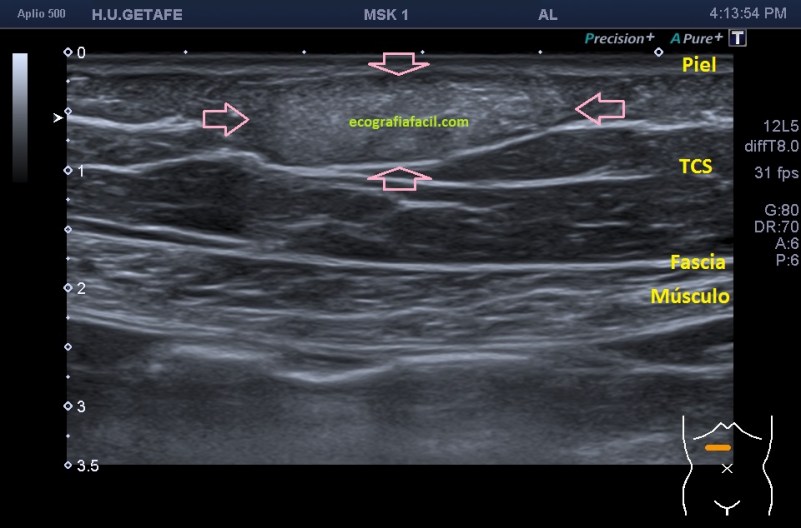

Normalmente encontraremos una lesión bien definida, hiperecogénica o isoecogénica con los márgenes definidos, en ocasiones lobulados, pero casi siempre ovalados con su eje largo paralelo a la piel en el plano subcutáneo y sin vascularización. Así, mira:

La estructura que estamos estudiando en este Caso 1, en las imágenes 1 a 6, es el estudio de protocolo de cualquier lesión, localización (flechas rosas), medición, vascularización. La 7 te marca una situación habitual en el estudio de los lipomas, y es que la paciente se nota un bulto, pero en la misma exploración descubrimos más, como es la pequeña lesión hiperecogénica que está justo al lado de la lesión mayor y palpable. Algunos de ellos, repito, pueden ser imperceptibles para la paciente, como era este caso. La imagen 8 es otra lesión próxima que sí era palpable.

En este caso las lesiones son todas hiperecogénicas comparativamente con el tejido hipoecogénico de la grasa del tejido celular subcutáneo. Son más o menos ovaladas, su eje largo es paralelo a la piel, no tienen vascularización y tienen medidas distintas. El diagnóstico final fue de lipomas. La paciente tenía más en la extremidades.